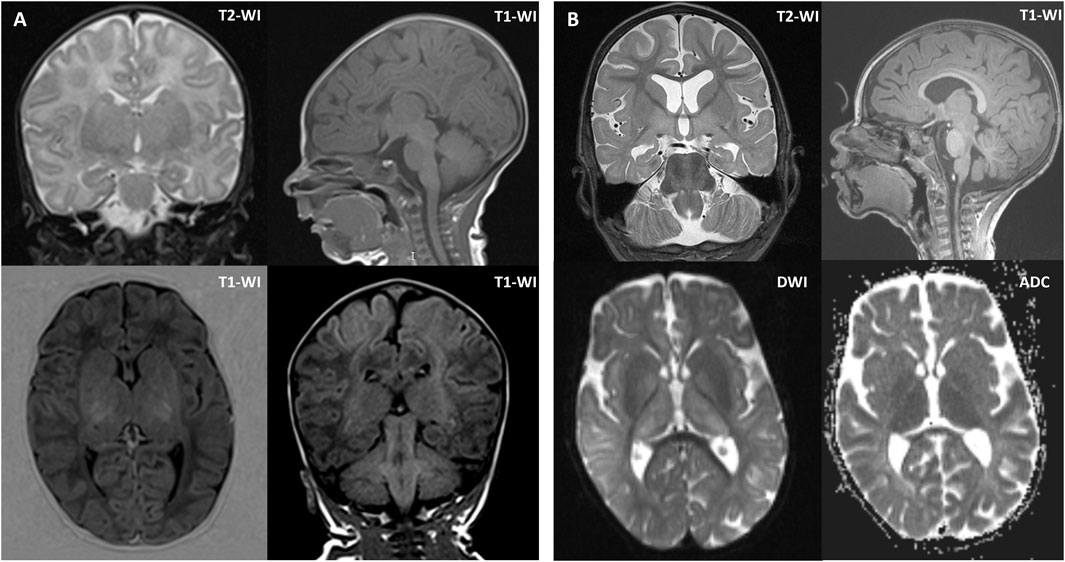

Brain magnetic resonance imaging (MRI) was performed twice. The first MRI, performed at 1 month of age, showed increased MR signals and volume in the putamen and thalamus bilaterally. The second MRI, performed at 2 years and 1 month of age, revealed atrophy of the cerebral cortex and corpus callosum, a persistent lack of myelination, and periventricular leukopathy, hypomyelination of the deep white matter, and symmetrical enlargement of the putamen, thalamus, and red nucleus (Figure 1). A comparison of the two scans showed mild progression of cerebral atrophy and hypoplasia of the corpus callosum.

Figure 1. Brain MRI of the proband at 1 month of age (A) and 2 years and 1 month of age (B). (A) Brain MRI at 1 month of age showed symmetrically increased MR signal and volume of the putamen and thalamus. (B) Brain MRI at 2 years and 1 month of age showed mild diffuse cerebral atrophy without cortical architectural disruption, except for hypoplasia of the corpus callosum, periventricular white matter alterations, hypomyelination of the deep white matter, and symmetrical enlargement of the putamen, thalamus, and red nucleus. Axial diffusion-weighted imaging (DWI) and apparent diffusion coefficient (ADC) images showed restricted diffusion in the basal ganglia. Coronal T2-weighted images (T2-WI) at 1 month of age and 2 years and 1 month of age revealed mild progression of cerebral atrophy. Sagittal T1-weighted images (T1-WI) at 1 month of age and 2 years and 1 month of age showed mild progression of hypoplasia of the corpus callosum.